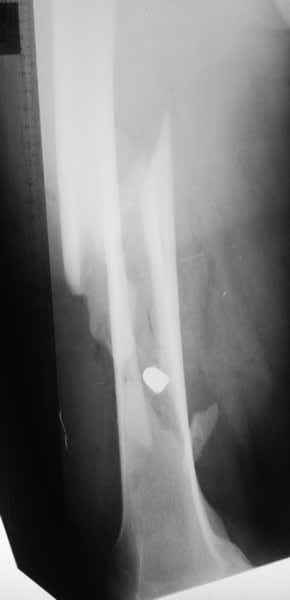

Пуля от ПМ - очевидно, что ранение было т.н. низкоэнегетическим, что подтверждается в том числе спокойным состоянием мягких тканей в этом, уже отсроченном периоде.

Характерным признаком травмы с низкой кинетической энергией является отсутствие "мультифрагментации и кавитации", и поэтому в данном случае лечение можно проводить любым доступным методом.

Здесь представлены несколько случаев лечения огнестрельного перелома

1 Проксимальный перелом бедра, антеградный гвоздь